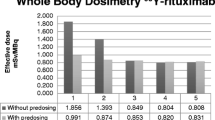

Extended imaging and data collection protocol

All 27 patients in our extended 131I-rituximab RIT dosimetric study underwent a standard treatment protocol as described previously [1]. Briefly, humanised chimeric rituximab was radiolabelled in-house by the chloramine-T method. An initial tracer activity of 200 MBq 131I-rituximab was injected intravenously. Subsequently, whole-body gamma camera imaging at 1 h and 4 and 7 days was used to determine the effective half-life of the radioiodinated antibody. The therapy activity was then computed using our modification of the total body dosimetry quantitation approach proposed by Wahl [2, 3] which takes into account lean body weight and whole-body clearance rate.

Measurements of activity concentration in spine, pelvis and femoral compartments correlated very closely as assessed using the Pearson correlation test (p<0.001, Fig. 4). Furthermore, there was a statistically significant linear relationship (p<0.001, Fig. 5) between extrapolated corrected activity concentration and each of the parameters associated with administered activity (activity administered per unit of weight, per unit of height and per unit of BSA). The best correlation and the most significant linear relationship were found between spinal marrow activity concentration and administered activity per metre squared of BSA (r=0.767, t=6.65, p<0.001; Fig. 5c).

We tested both of these assumptions against our data and measurements of marrow uptake using SPECT/CT scanning in patients receiving 131I-rituximab RIT for relapsed or refractory NHL. A strong statistically significant correlation between whole-body effective half-life and marrow half-life (Pearson correlation test, r=0.919, p=0.001) as well as a statistically significant linear relationship (t=4.669, p=0.01) was demonstrated. Furthermore, we found that the activity concentration in red marrow at the time of administration was directly proportional to the administered activity per unit of weight, height and BSA (r=0.767, t=6.65, p<0.001). Therefore, we conclude that both assumptions have been validated and are correct. Thus the relatively simple total body dosimetry calculation may be appropriately used as a surrogate for haematopoietic marrow dosimetry.

Conclusion

We have validated a practical prospective individual dosimetry method using whole body as a surrogate organ for the estimation of red marrow dose [1–3] for RIT of NHL. This method is based upon scaling the administered activity using whole-body effective half-life and ideal weight of a patient in the expectation that absorbed dose to bone marrow will be directly proportional to the effective half-life of radiolabelled antibody in the whole body and that it will decrease linearly with the ideal weight of a patient. We measured marrow uptake using a novel technique employing SPECT/CT hybrid imaging and found that whole-body effective half-life and red marrow half-life strongly correlated (p=0.001) and demonstrated a statistically significant linear relationship (t=4.669, p=0.01), showing their equivalence. Furthermore, marrow uptake correlated strongly (p<0.001) with the administered activity per unit of weight, height or BSA, demonstrating a statistically significant relationship between marrow uptake and activity administered per unit of weight, height or BSA. The most significant relationship was that between marrow activity concentration and activity administered and unit of BSA (t=6.65, p<0.001). We conclude that whole body may be safely used as a surrogate organ for haemopoietically active marrow for prospective individualised critical organ dosimetry to ensure safe, effective 131I-rituximab RIT of NHL. There have been no adverse clinical events in our patients treated using methodology limiting the prescribed radiation absorbed dose to total body to 0.75 Gy.